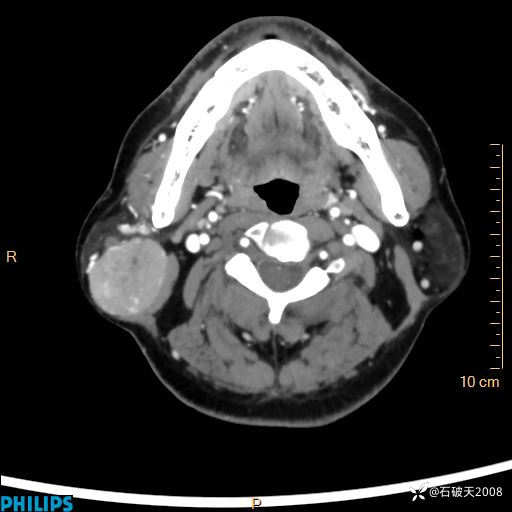

病例分享:颈部占位,一周后公布病理

男 57岁 主 诉:发现右侧颌下肿物1月余。

现病史:1月余前家属发现右侧颌下肿物。局部皮肤无红肿、热痛,无吞咽困难,无异物感,无恶心、呕吐,无头痛、头晕,无胸闷、胸痛,无发热、咳嗽、咳痰及呼吸困难。于我院行体表肿块彩超检查(2024.03.15我院)示:右侧耳下皮下软组织内低回声,未治疗。今为进一步治疗门诊以“腮腺肿瘤”为诊断收住我科,发病来患者神志清,精神可,饮食、睡眠及大小便正常,体重无明显下降。

平扫